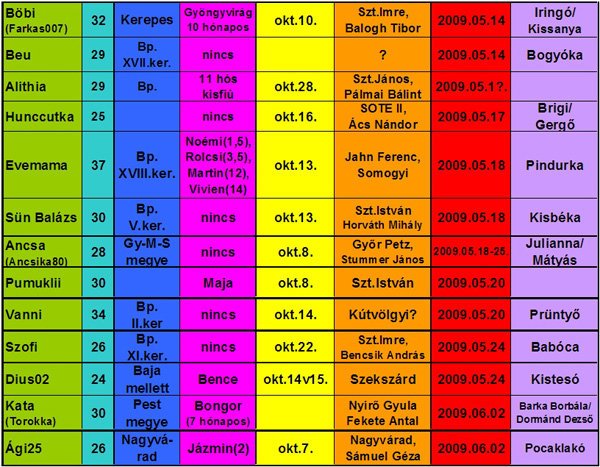

Annus nagyon jók a képek. kis ALien-nek néznek ki... szép az élet...

5mm a baba

5mm a baba  8 mm a baba